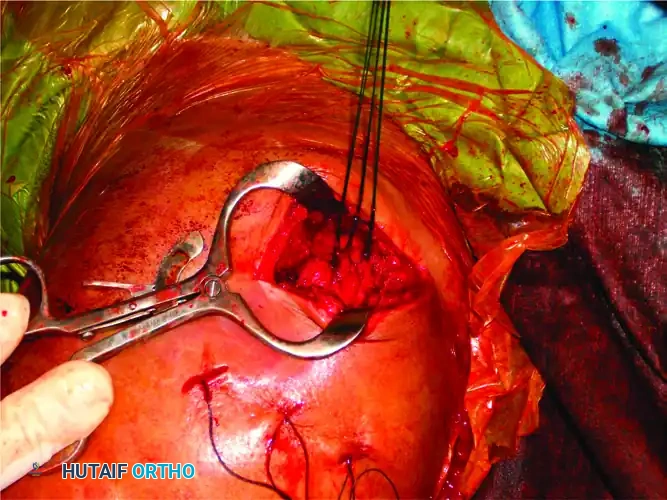

Clinical photograph demonstrating the proximal exposure. The plate is prepared to be slid distally beneath the axillary nerve.

- Positioning on the Bare Spot: While positioning the plate, ensure it rests strictly on the "bare spot" of the lateral cortex, located posterior to the bicipital groove. This avoids injury to the ascending branch of the anterior circumflex humeral artery.

- Distal Fixation: Secure the plate to the humeral shaft through a lower soft tissue window created distal to the axillary nerve.

The plate is successfully secured to the humeral shaft. The axillary nerve is clearly visible, safely crossing over the plate at the head-shaft junction.